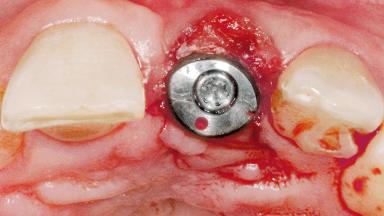

Late Flapless Placement of an Implant in a Maxillary Left Central Incisor Site

Type of Implants One-Piece

Attachment One-Piece